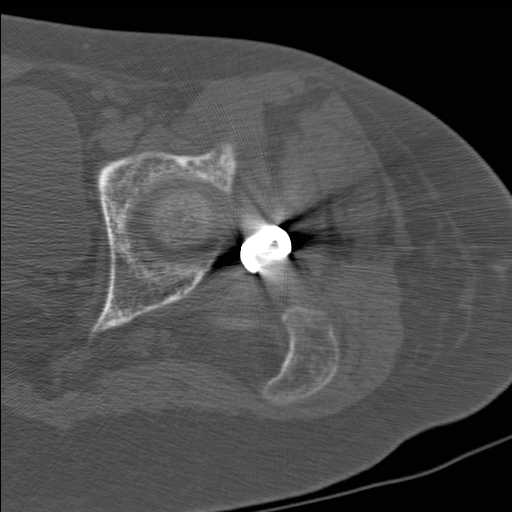

Затем переведена в наше учреждение. 18 июня выполнена операция, детали где , кто и как уточнять не имеет смысла( из протокола операции: выполнялась передняя артротомия, репозиция под визуальным контролем) . Учитывая характер выполненного остеосинтеза, после операции постельный режим 6 недель. Снимки в хронологии все выкладываю. КТ контроль сделан 2.09.16. для оценки состояния головки бедра. Помогите, определиться с дальнейшей тактикой.

В динамике. Замыкательных пластинок вроде нет. Даст Бог...

согласен с Александром Николаевичем, надо пытаться сохранить сустав (в т.ч. его страдающее кровоснабжение. Судя по КТ Сохраняется ретроверсия шейки бедра. Вероятны трудности с репозицией последней. Для создания правильного направления шеечных винтов (Винта) возможно придется делать вальгусно-антекурвационную межвертельную остетомию, тем самым произвести разгибание в т/бедренном суставе проксимального отломка. И ретроверсия станет в большей степени вальгусом. То есть точка входа для гвоздя должна быть кзади от торчащей части прорезавшегося клинка со всеми вытекающими перемещениями проксимальной части.